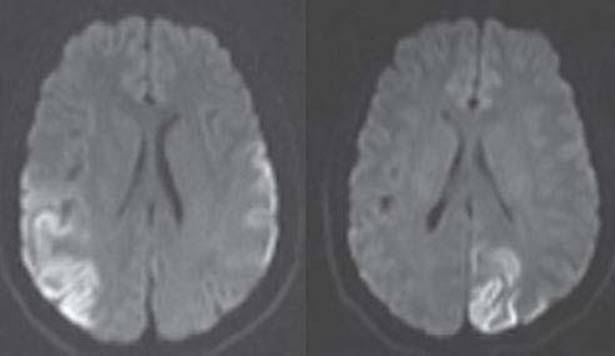

97. A 15-year-old boy with growth and psychomotor retardation, sensorineural hearing loss, frequent headaches, and seizures presents for evaluation of multiple stroke-like episodes. Two MRIs from different time points are shown in Figure 14.23. Lactate level is found to be elevated. Which of the following is the most likely diagnosis?

FIGURE 14.23 Axial DWI MRI from two different time points

b. Mitochondrial encephalopathy, lactic acidosis, and strokes